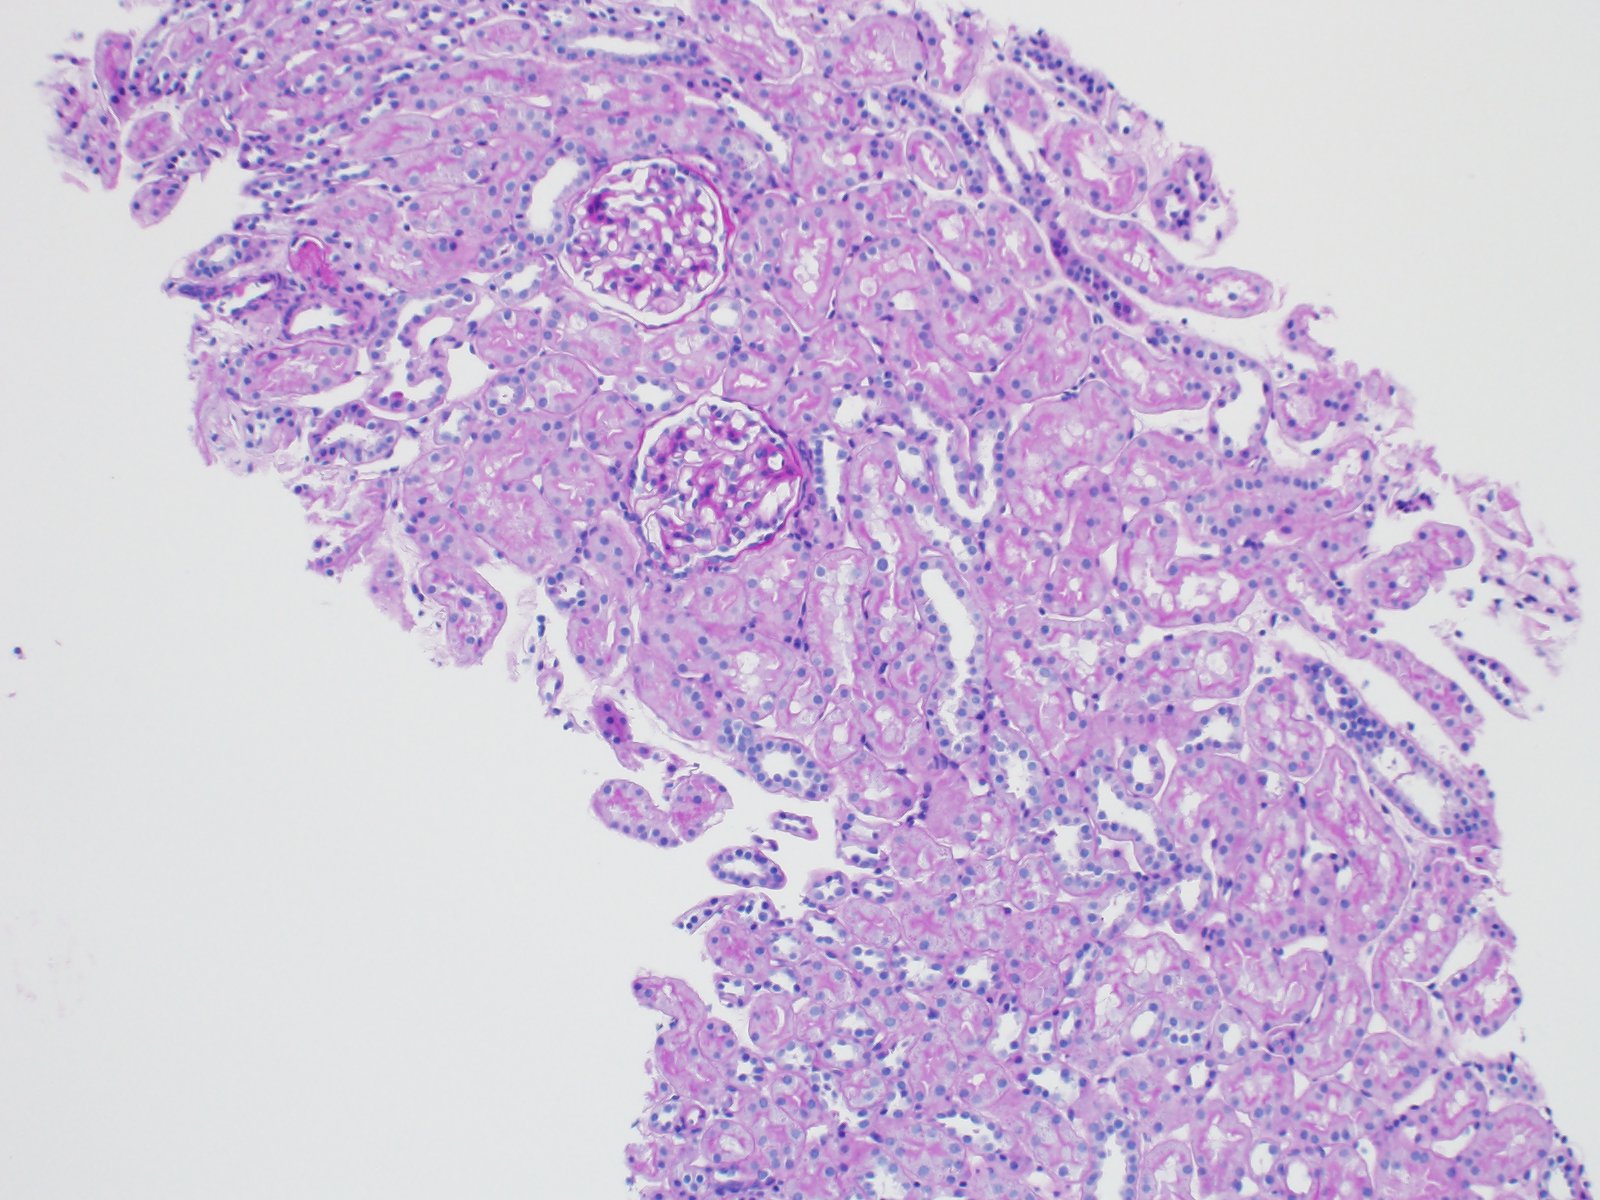

2. Are the capillary loops open?

3. Is Bowman’s space open?

4. Is the mesangial space expanded?

5. Is there proliferation of mesangial, parietal, or endothelial cells?

6. Are the tubules “back-to-back” with a healthy brush border?